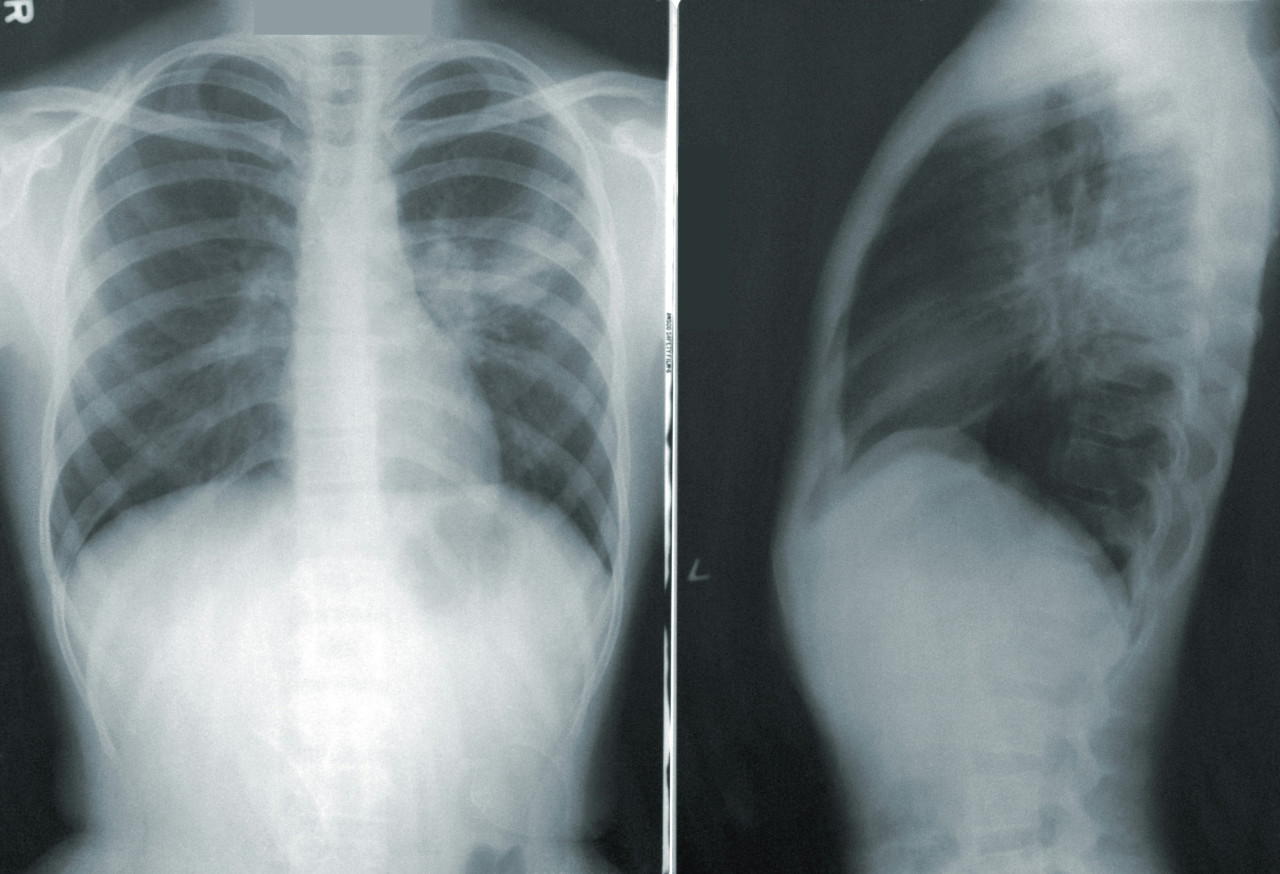

La mitad de la muestra recibió lorlatinib. Al resto, por su parte, le administraron crizotinib, un fármaco de generación anterior.

El producto redujo el progreso de la enfermedad. Foto: Unsplash

Los resultados fueron asombrosos y esperanzadores: luego de cinco años de seguimiento, el 60% de los pacientes tratados con este producto no tuvieron progresos de la enfermedad.

"Estamos hablando de pacientes con enfermedad metastásica avanzada, por lo que se trata de un hallazgo sin precedentes", dijo a la AFP Despina Thomaidou, de la empresa Pfizer. "Hay una reducción del 81% en el riesgo de progresión o muerte", agregó.